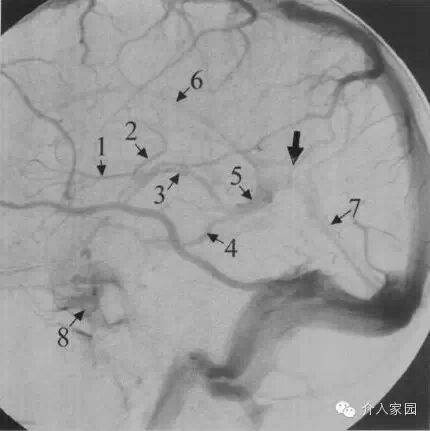

1、上吻合靜脈 2、額升靜脈 3、靜脈角 4、透明隔靜脈 5、大腦中淺靜脈 6、海綿竇 7、岩下竇 8、乙狀竇 9、中央溝靜脈 10、上矢狀竇

11、頂升靜脈 12、下矢狀竇 13、丘紋靜脈 14、胼周後靜脈 15、大腦內靜脈 16、枕升靜脈 17、大腦大靜脈 18、側腦室下靜脈 19、基底靜脈

20、直竇 21、大腦下靜脈 22、竇彙 23、橫竇